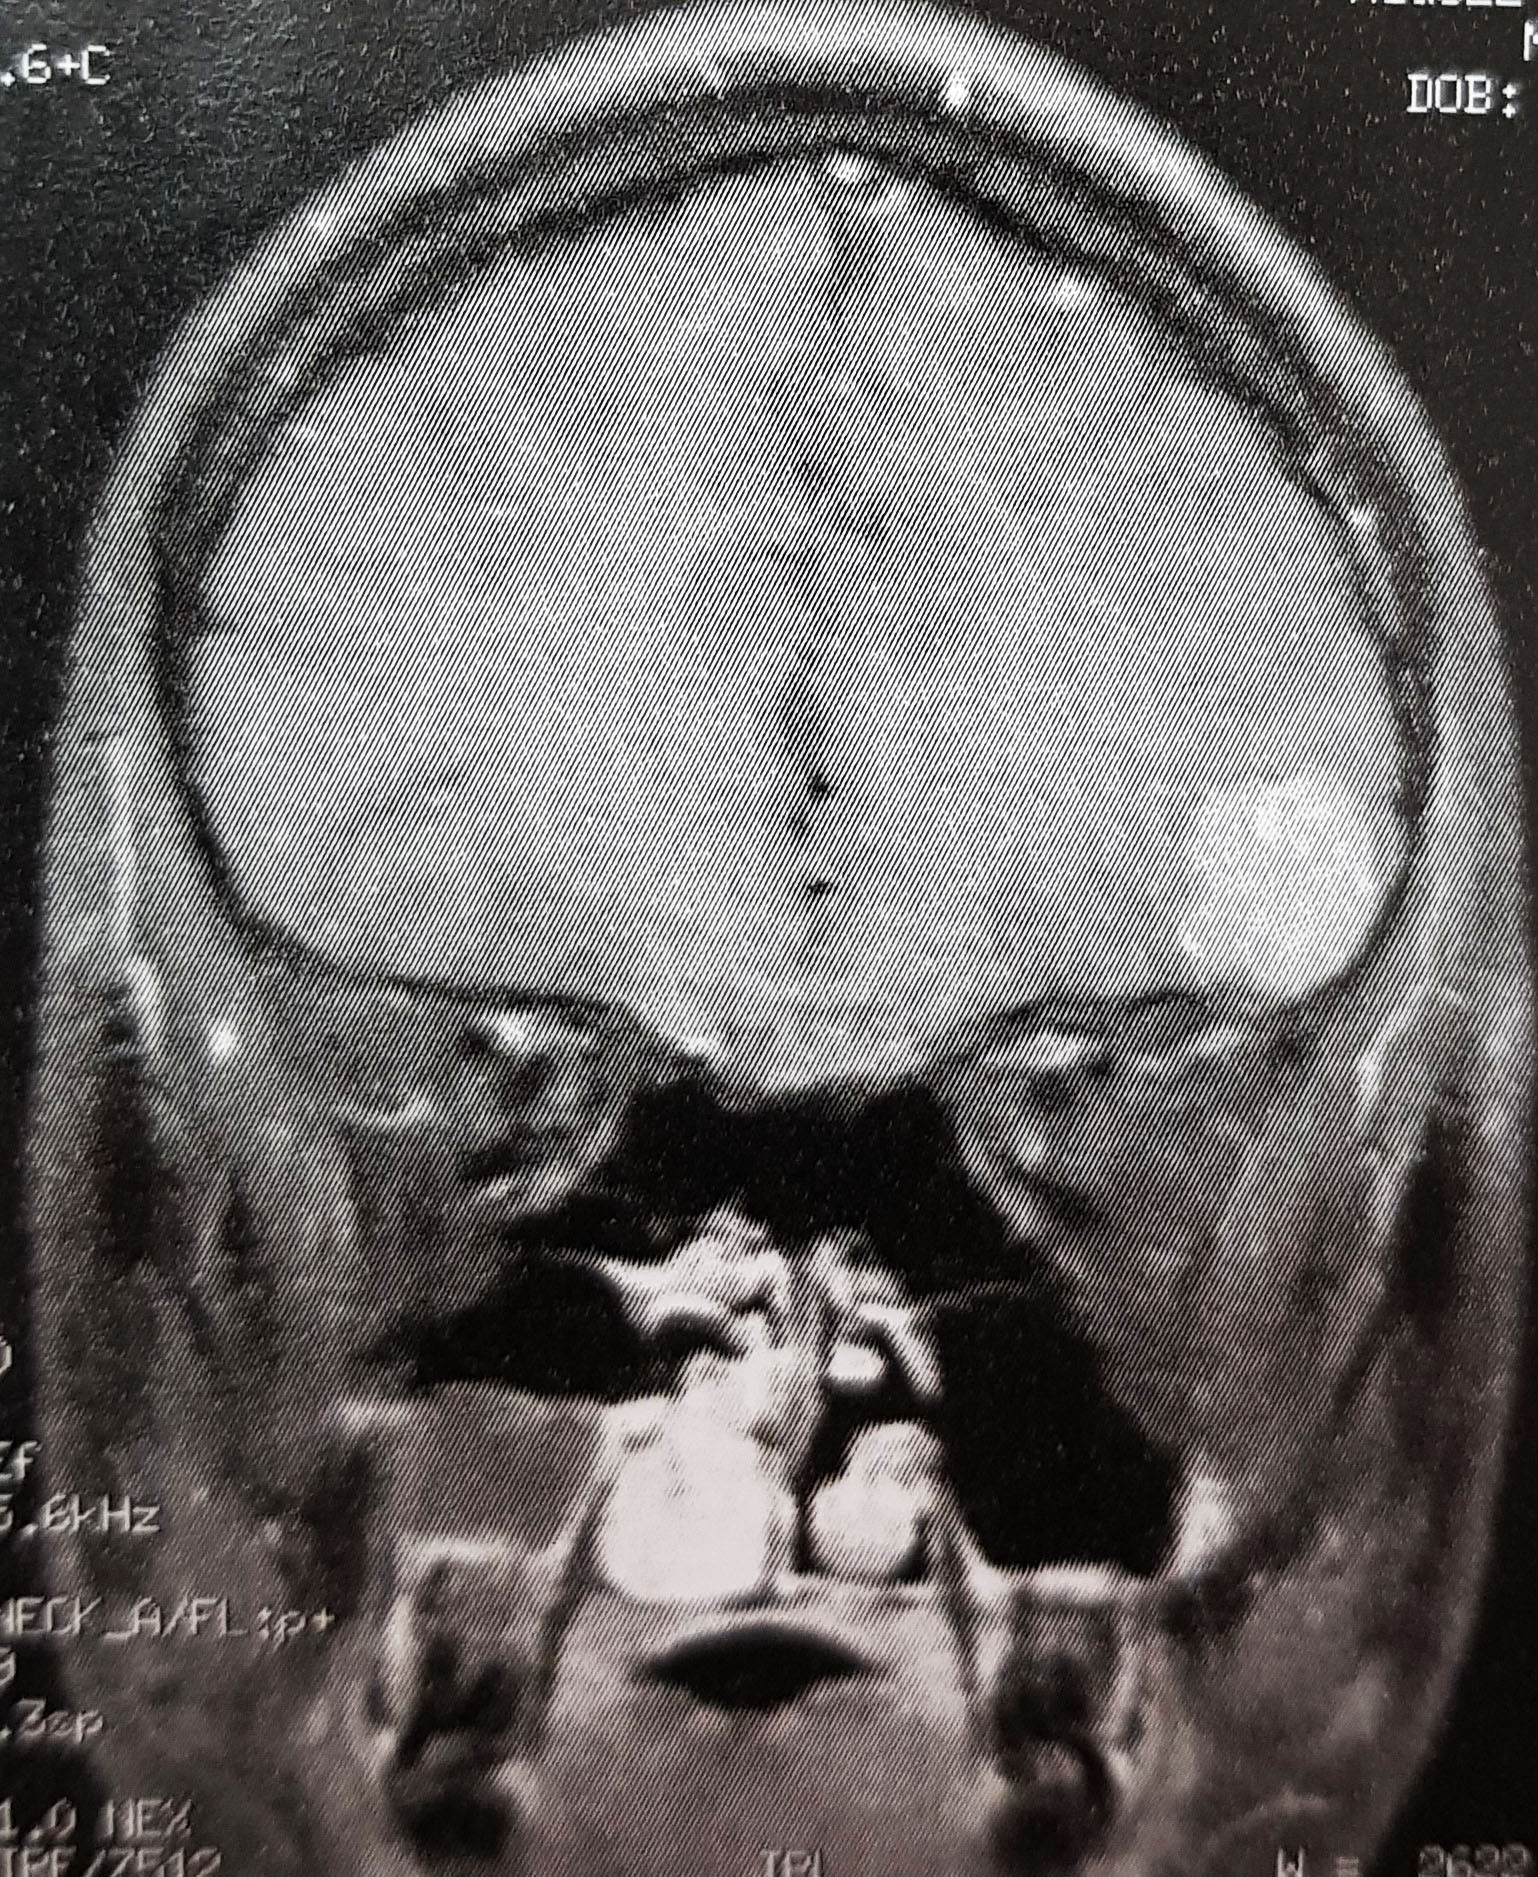

Ressonância magnética: Formação neoplásica expansiva de difícil caratcerização ( intra ou extra-axial ?) em fossa craniana anterior com realce intenso após injeção de contraste com espessamento e realce de planos paquimeningeais adjacentes, medindo 2,4cm